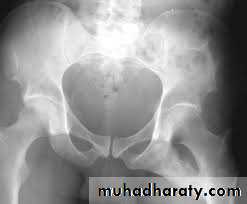

HIP DISLOCATION

Injuries of the hip and femur

The magnitude of force needed to dislocate the hip joint particularly well-contained by virtue of its bony and soft-tissue anatomy.

is so great that the dislocation is often associated with fractures - either around the joint or elsewhere in the same limb.

Hip dislocations are classified according to

the direction

of the femoral head displacement:

Traumatic Dislocations of the hip.

Posterior.

Anterior.

Central.

Posterior dislocation:

4 out of 5 traumatic hip dislocations are posterior.

Usually occur in road traffic accident when the knee striking the dashboard

the femoral head is forced out of its socket sometimes associated with fracture.

The golden role is to x ray the pelvis in every case of sever injure

and with femoral fracture to include both the hip and knee.

Radiological examinations

X-R AP view we can see the dislocation with or without associated fracture posterior wall of the acetabulum,

or fracture head of the femur,

And neck of femur.